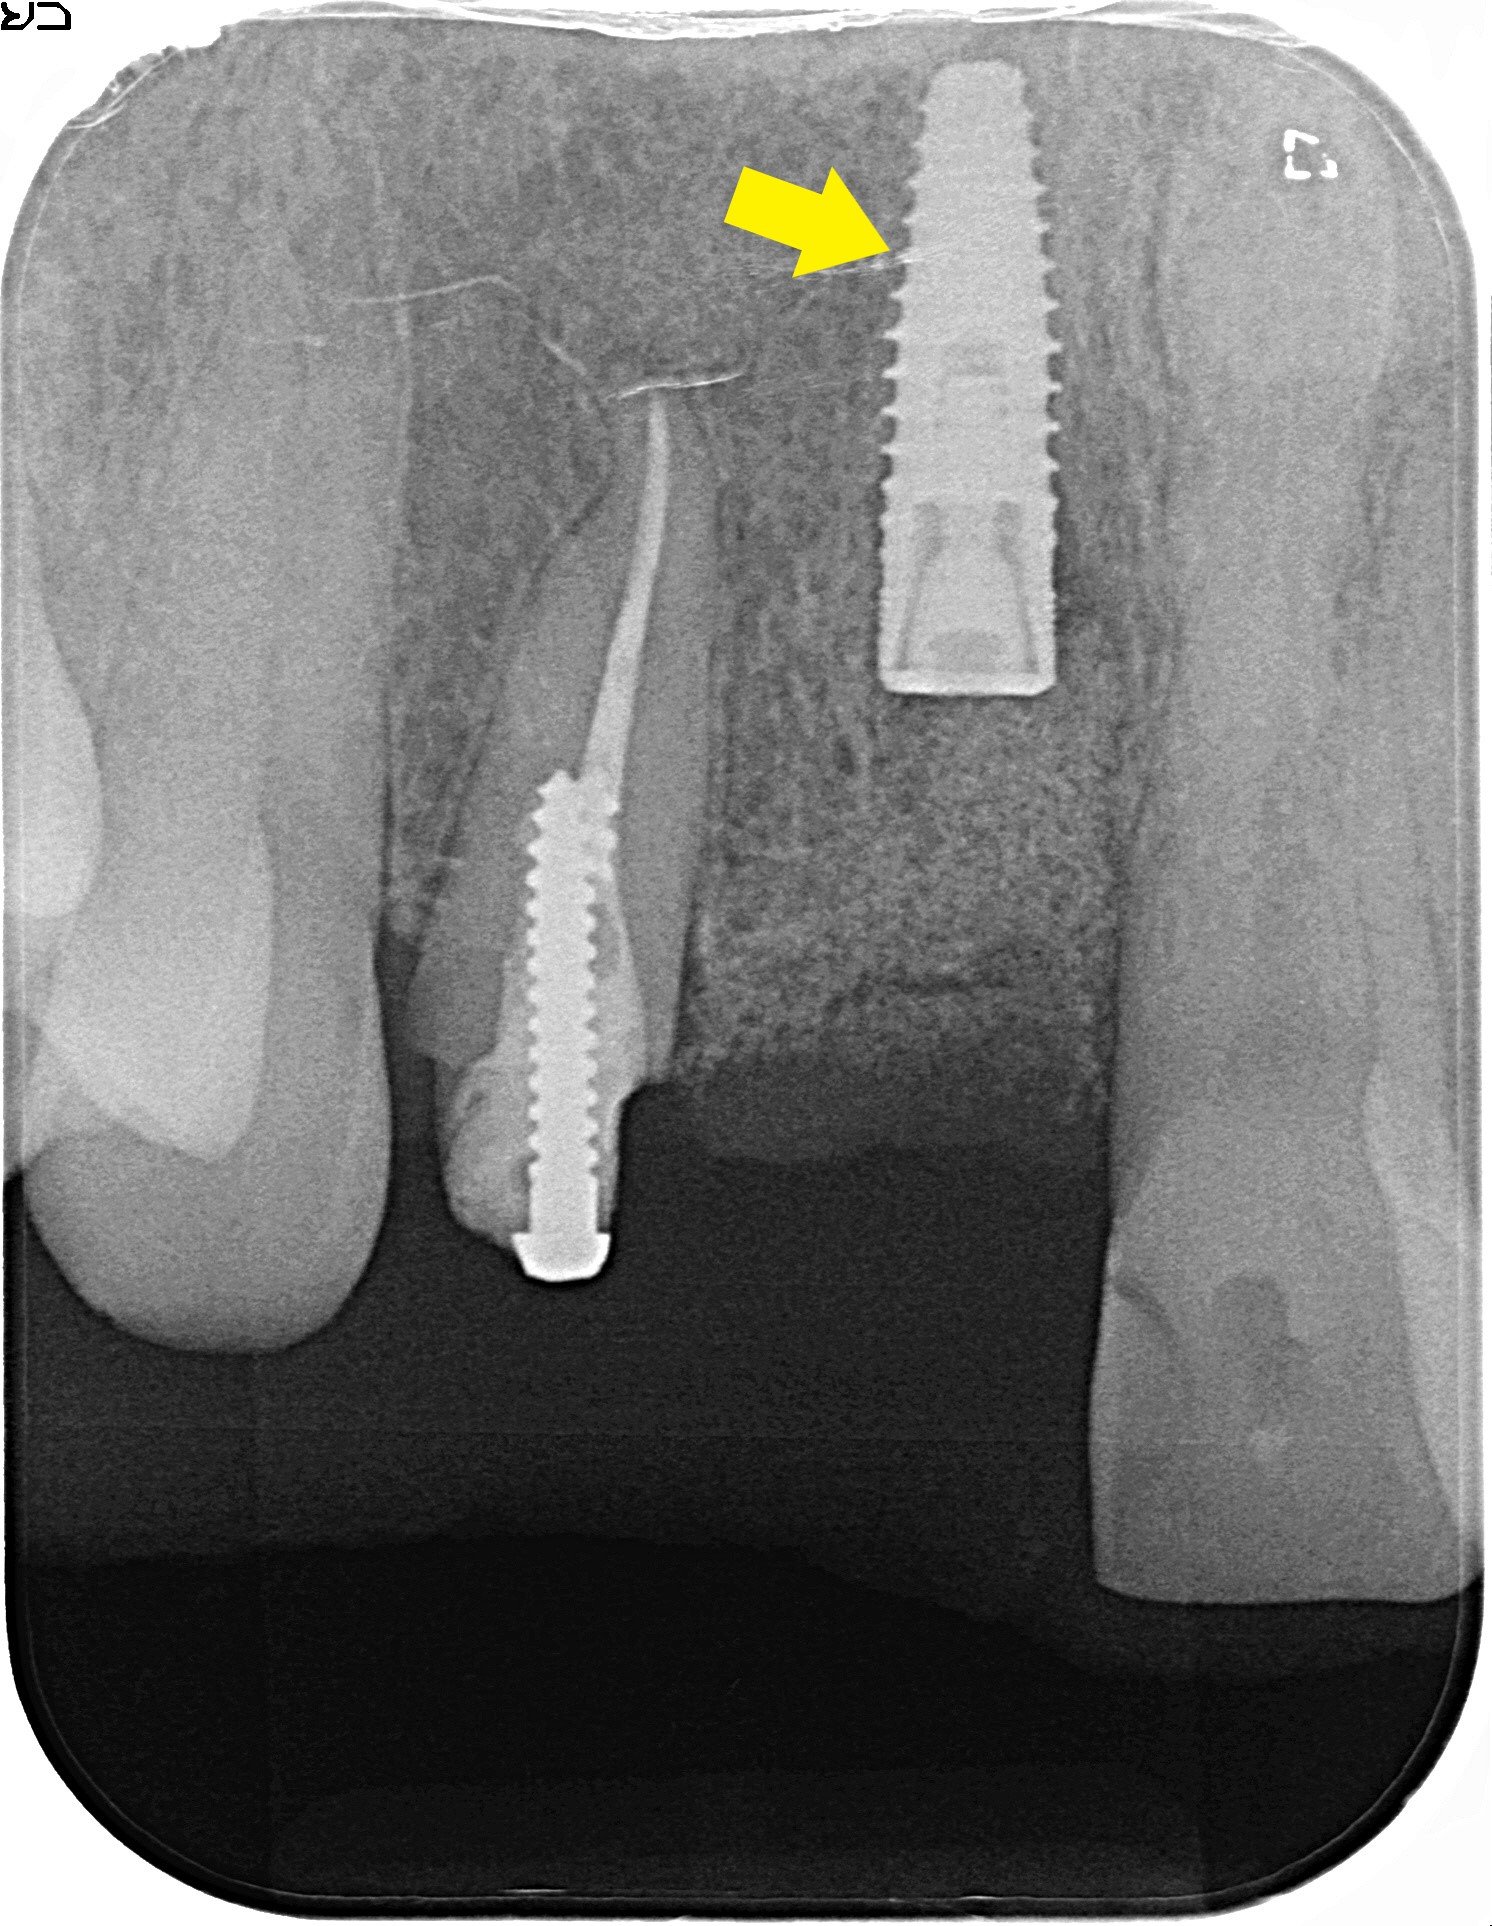

抜歯後の骨はクレーター状に欠損していたため、インプラント埋入時には人工骨を使用した骨造成術(GBR)を併用しました。

【CT画像・矯正計画】

前歯部のCT画像で、左上前歯(緑色矢印)を内側に移動させる計画を立てました。通常、プチ矯正では前歯を内側に引っ込める治療は難しく、アライナー矯正やワイヤーによる全顎矯正が適応範囲です。

本症例では、右上前歯をインプラントで固定したことで、強固な固定源を得られたため、左上前歯を内側に動かすことが可能となりました。